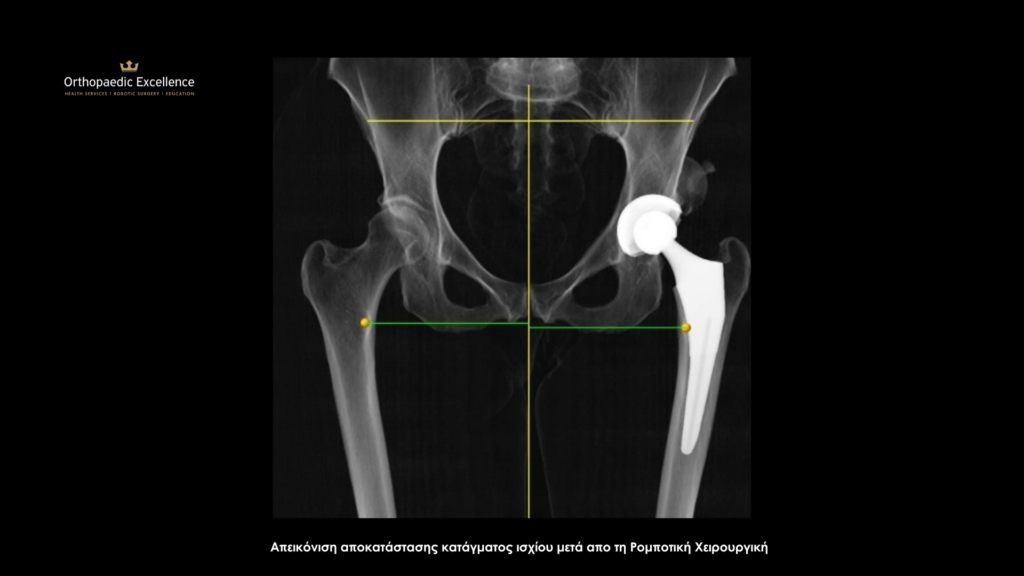

Αποκατάσταση Κατάγματος ισχίου με το Ρομποτικό σύστημα ΜΑΚΟ